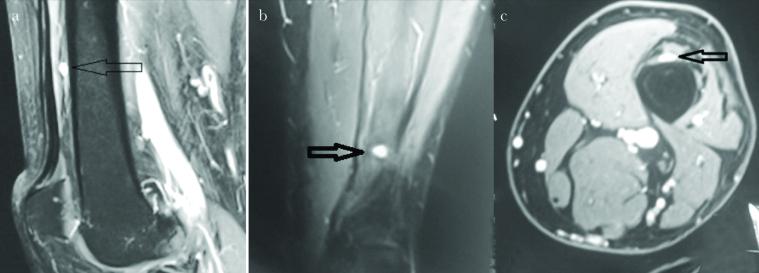

Lower Extremity Neuroma: An Unusual Cause of Leg Pain.

Turk J Anaesthesiol Reanim. 2020 Oct;48(5):434-435. doi: 10.5152/TJAR.2020.88615. Epub 2020 Apr 27.

https://cdn.ncbi.nlm.nih.gov/pmc/blobs/18fb/7556649/371f62c50ff4/TJAR-48-5-434-g01.jpg